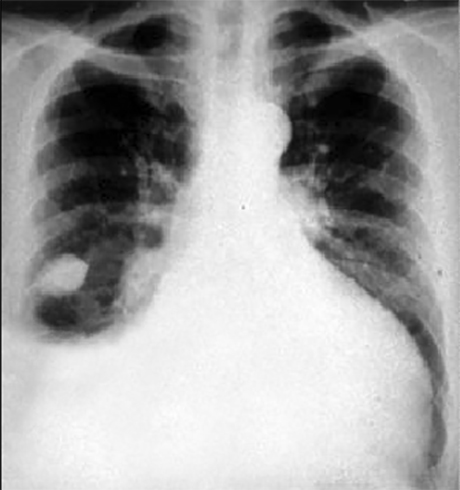

Our Patient's PA and Lateral

Click on the xrays to enlarge them.

Choose the best interpretation of the chest X rays:

Cardiomegaly, pulmonary venous congestion & pleural effusion